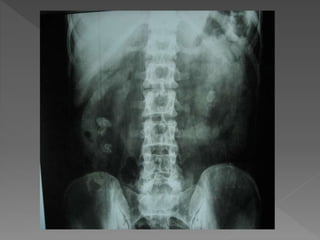

 The plain film demonstrates

 The plainfilm demonstrates calcification within distended upper pole calyces